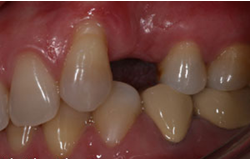

Implant thay thế 1 răng

![]() |

| Mất 1 răng |

Trong tất cả các ca implant răng cửa, bệnh nhân đều có răng tạm trong thời gian chờ phục hình chính thức trên Implant. Như vậy, các hoạt động giao tiếp xã hội của bạn đều diễn ra bình thường.

Phục hình răng trên implant

| Gắn răng sứ trên Implant R24 |